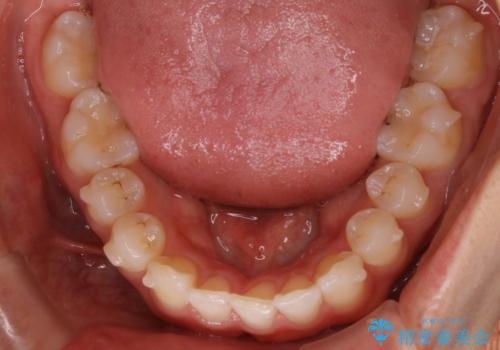

【非抜歯】下の前歯が1本少ない場合の矯正治療

- 前歯のガタつきを主訴に来院されました。

生まれつき下の前歯が1本少なく、その分のスペースを上の前歯がガタつくことで埋めているという状況でした。

上下それぞれのガタつきをとっていく過程で、歯1本分のスペースの差を、上顎の前歯のIPRで調整して並べる方法をご提案させていただきました。